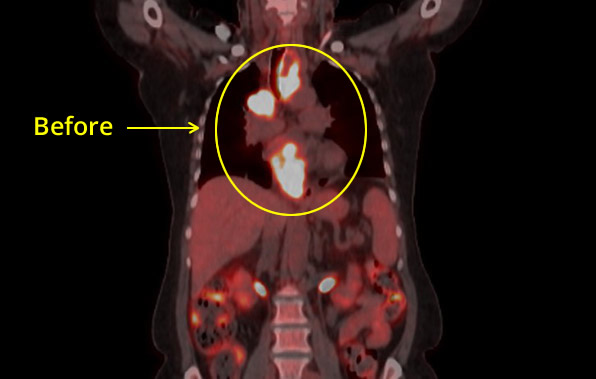

Esophageal CXR Before